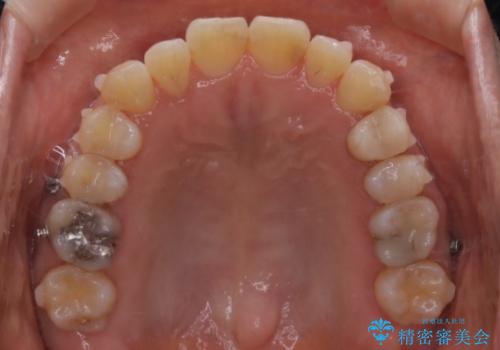

- 右上の2番目の歯が内側に入っているのと、下の前歯のがたつきが気になるとご相談にいらした方です。

上下左右の歯を後ろに動かして歯を並べるスペースを確保し、内側に入っていた歯を綺麗に並べ、前歯の中心もお顔の中心に合うようにしました。

矯正用アンカースクリューを埋入し、上下左右の歯を後ろに動かすことで歯を並べるスペースを作りました。